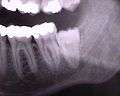

ചിലരിൽ മോണയിൽ കീറലുണ്ടാക്കിക്കൊടുത്താൽ വിവേകദന്തങ്ങൾ കുഴപ്പമില്ലാതെ വളർന്നു വന്നുകൊള്ളും. മുൻകൂട്ടി എക്സ്റേ എടുത്ത് നോക്കിയാൽ ഈ പല്ലുകൾക്ക് പുറത്ത് വരാൻ സ്ഥലമുണ്ടോ എന്നു അറിയാനാകും. മോണയിൽ അല്ലെങ്കിൽ എല്ലിൽ കുടുങ്ങി പോകുക, വീക്കവും വേദനയും ഉണ്ടാവുക എന്നീ പ്രശ്നങ്ങൾ ഉണ്ടെങ്കിൽ ശസ്ത്രക്രിയ മൂലം നീക്കം ചെയേണ്ടി വരും. മേൽവരിയിലെ വിവേകദന്തങ്ങൾ നീക്കം ചെയ്യുന്നത് താരതമ്യേന എളുപ്പമാണ്. വിവേകദന്തങ്ങൾ പ്രശ്നമില്ലാതെ വളരുന്നവരും ശ്രദ്ധിക്കേണ്ടതുണ്ടു. ഭക്ഷണാവശിഷ്ടങ്ങൾ അടിഞ്ഞുകൂടി അണുബാധ വരാൻ സാദ്ധ്യത ഏറെയാണ്.